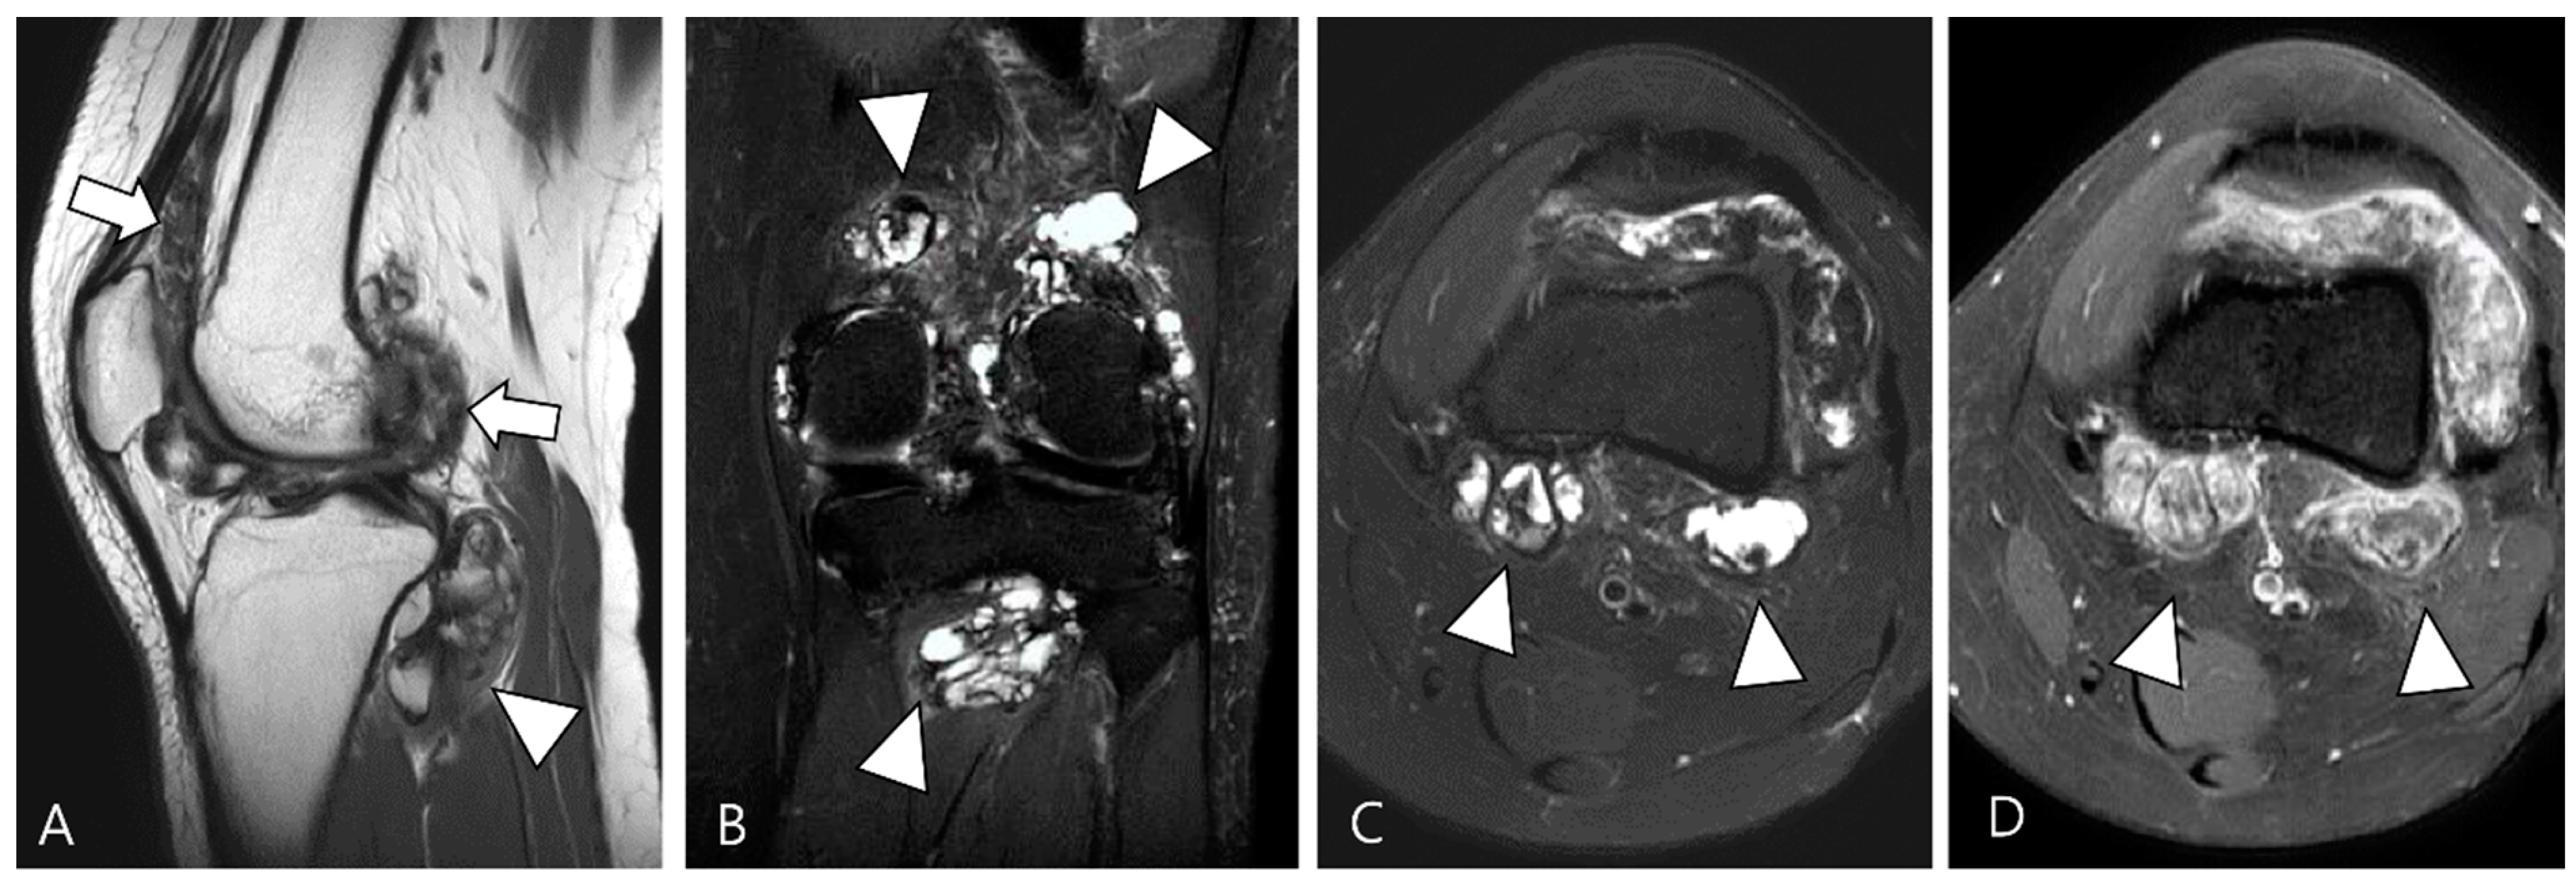

3.1. Differential Diagnoses of Intra-Articular D-TSGCT

3.1.1. Hemosiderotic Synovitis

3.1.2. Synovial Chondromatosis

3.1.3. Dialysis-Related Amyloid Arthropathy

3.1.4. Chronic Rheumatoid Arthritis

3.1.5. Tophaceous Gout